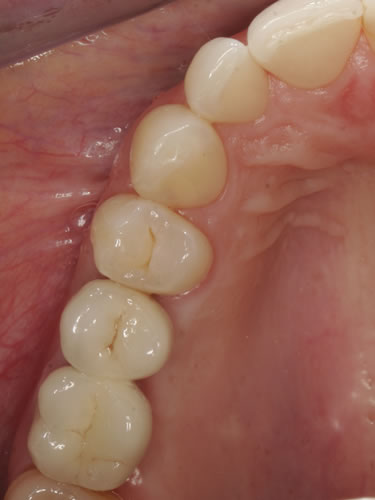

3.4 Reduzierte Bezahnung

Wenn viele Zähne fehlen und nur noch einige erhaltungswürdige Zähne vorhanden sind, die in den neuen Zahnersatz mit einbezogen werden können, dann spricht man von einer reduzierten Bezahnung. Die prothetische Versorgung wird als Hybridkonstruktion bezeichnet, da sie sowohl auf natürlichen Zähnen als auch auf Implantaten befestigt wird. Die Versorgung kann sowohl festsitzend - verschraubt oder zementiert - gestaltet werden (Abb. 3.24, 3.25), aber auch herausnehmbar, wobei dann häufig teleskopierende Konzepte verwendet werden (Abb. 3.26, 3.27).

Abb. 3.24: Festsitzende Hybridbrücke auf 4 Zähnen und 6 Implantaten.

Abb. 3.25: Brücken vor der Eingliederung.

Abb. 3.26: Hybridversorgung einer reduzierten Oberkieferbezahnung auf 4 Zähnen und 3 Implantaten.

Abb. 3.27: Ansicht des gaumenfreien, herausnehmbaren Zahnersatzes.

3.5 Reduzierte Bezahnung

Bei einer Einzelzahnlücke handelt es sich um eine zahnbegrenzte Lücke, bei der nur ein Zahn fehlt. Häufig sind die Nachbarzähne kariesfrei und nicht überkronungsbedürftig oder schon mit Zahnersatz versorgt, so dass eine Implantatversorgung eine sinnvolle Alternative zur konventionellen Brücke ist (Abb. 3.28, 3.29).

Abb. 3.28: Einzelzahnlücke im Unterkieferseitenbereich mit eingesetztem Implantat.

Abb. 3.29: Zementierte „unsichtbare“ Implantatkrone.